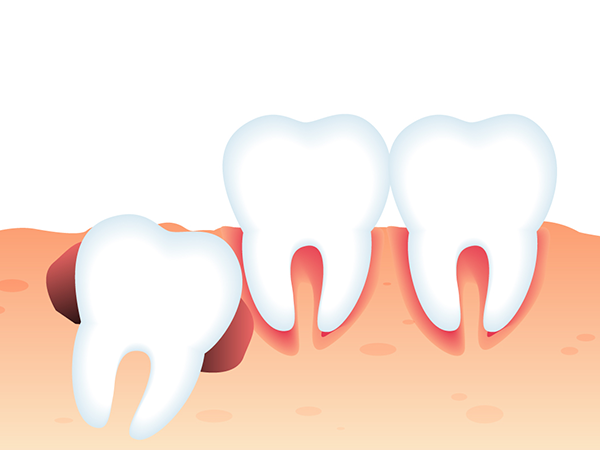

- 사랑니가 겉으로 보이지 않는 경우

- 사랑니가 매복되어 있는 경우에는 많은 경우는 아니지만, 치아를 둘러싸고 있는 치배(치아주머니)에 물이 차서 물혹이 되거나 세포가 변형되어 사랑니 주변 뼈를 점점 흡수할 수도 있습니다.